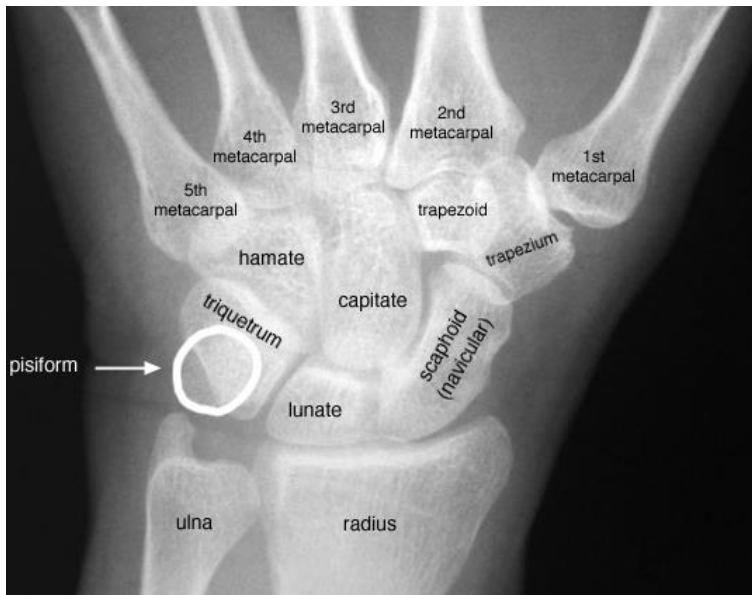

Scaphoid Fracture

- Diagnosis: Scaphoid Fracture.

- Clinical Sign: Tenderness in the anatomical snuffbox.

- Management: Thumb spica splint/cast. If X-ray is normal but tenderness is present, treat as a fracture and repeat X-ray in 10-14 days or order a CT/MRI.